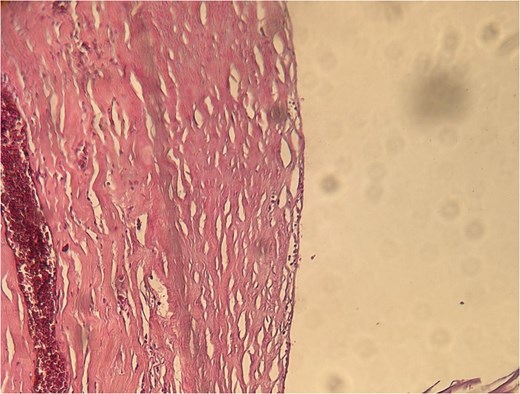

A 62-year-old Moroccan female with no significant medical history presented with right hypochondrial pain associated with nausea and vomiting for 1 month, in the absence of fever or systemic symptoms, with preserved general condition. Clinical examination revealed tenderness in the right hypochondrium. Abdominal ultrasound identified gallstones. During surgery, a cystic mass measuring 17 mm was incidentally discovered. The patient underwent cholecystectomy and cyst excision. Histopathological examination confirmed a cystic lymphangioma (Fig. 7). The patient’s postoperative course was uneventful.

Microscopic appearance of the cystic lymphangioma identified in Case 3.